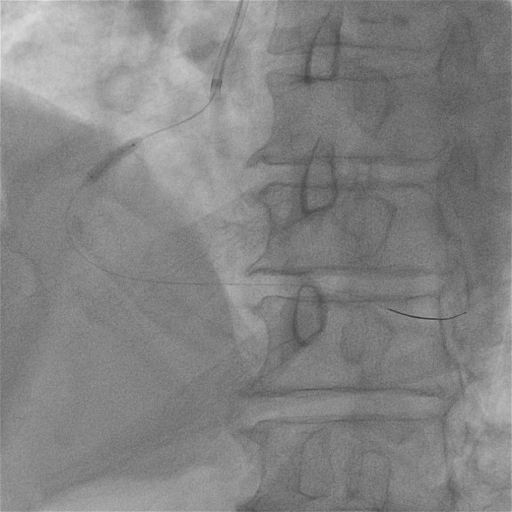

支架植入

于RCA病变处由远及近依次植入2.75*38mm、3.5*38mm、4.0*18mm支架各一枚。

后扩张

用3.0mm、3.5mm及4.0mm高压球囊充分对支架进行后扩张。

最终CAG和IVUS

术后造影及IVUS可见支架膨胀及贴壁良好,支架远近端未见夹层血肿。